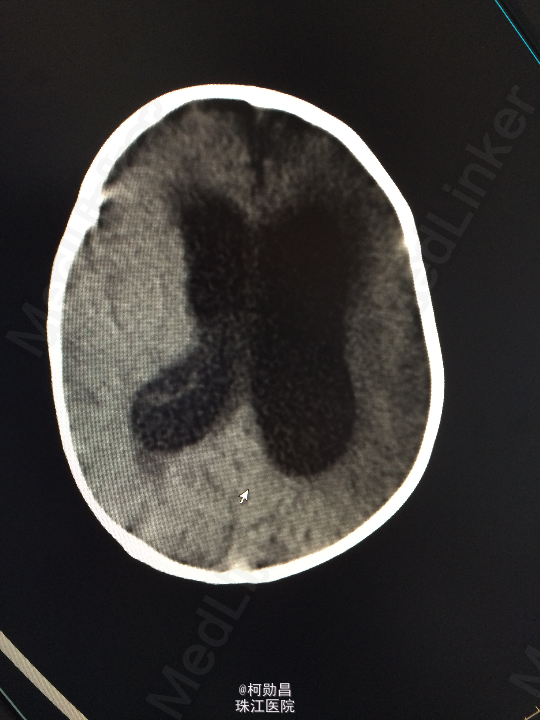

主诉:发热10天,抽搐3天 病史:患儿出生后8个月,因“发热10天,抽搐3天”入院,入院时体温39.3℃,神志不清,反应差。四肢肌张力增高,以双上肢肌力增高明显。病理征未引出。

查体:神志不清,四肢肌力增高 辅助检查:头颅CT提示脑积水并脑脊液外渗,幕上脑室扩张,右侧额颞叶硬膜下脑脊

诊断:化脓性脑膜炎伴脑积水 处理:予内科抗感染治疗,后行脑室腹腔引流术。